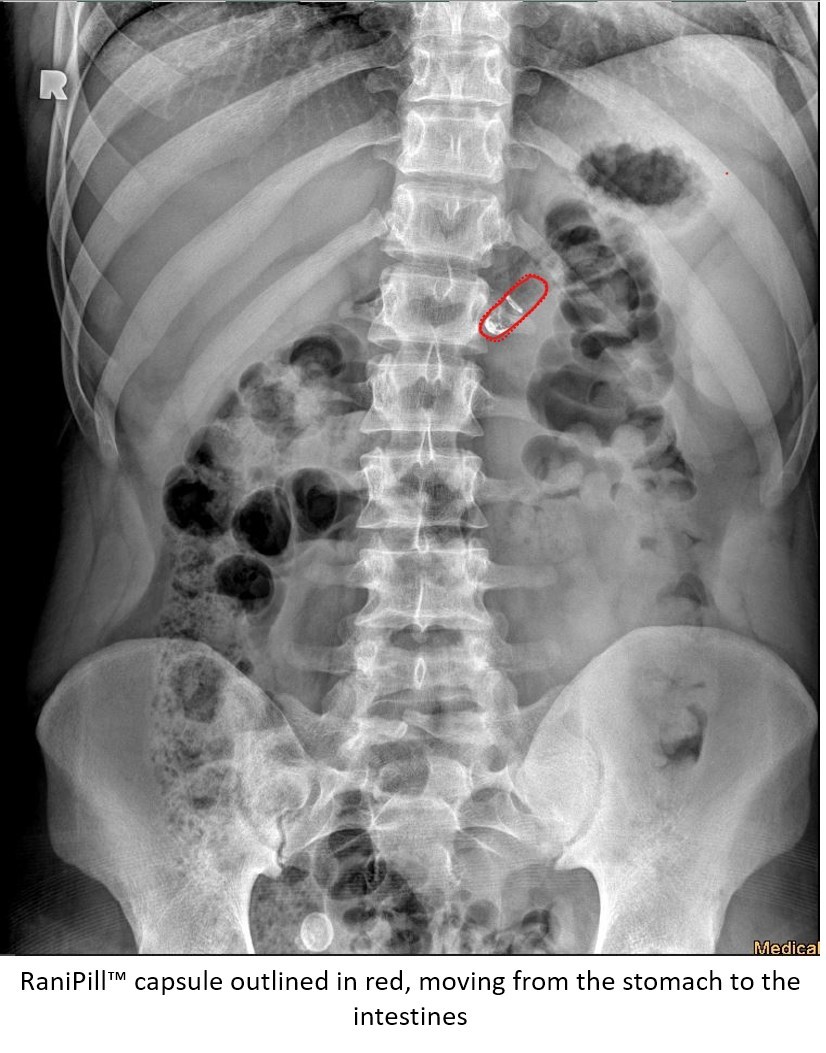

Here’s an interesting piece on Rani Therapeutics. Robotic pills are an interesting idea that has been floating around research facilities for a long time (MIT, in particular, has been pretty big on it), and it’s great to see someone take steps toward commercializing the concept. Specifically, the company’s product is designed to deliver subcutaneous injections to the small intestine.